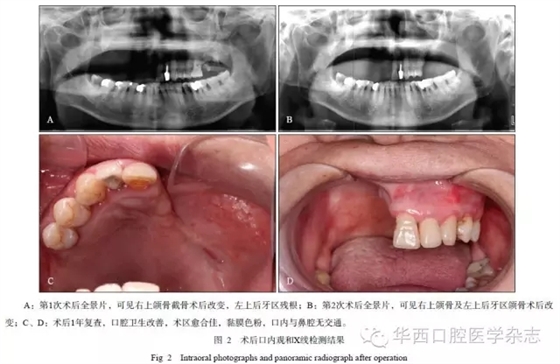

患者女,72歲,乳腺癌個(gè)人史20年、肺轉(zhuǎn)移13年。肺部轉(zhuǎn)移后,患者長期接受化療,接受過肺部放療。患者既往有飲酒史,每日飲白酒50mL,共飲6年,已戒20年;無抽煙習(xí)慣。2012年4月發(fā)現(xiàn)骨轉(zhuǎn)移后開始使用唑來膦酸,至入院前共計(jì)使用4mg×28個(gè)月。出現(xiàn)口腔癥狀(圖1)后行局部及全身抗炎治療,并接受了18次高壓氧倉治療?;颊呷朐汉螅邮?ldquo;上頜骨部分切除術(shù)”,術(shù)后愈合可。3個(gè)月后,左上頜后牙區(qū)再次發(fā)生藥物性頜骨骨髓炎,遂入院接受手術(shù)治療,術(shù)后愈合佳(圖2)。